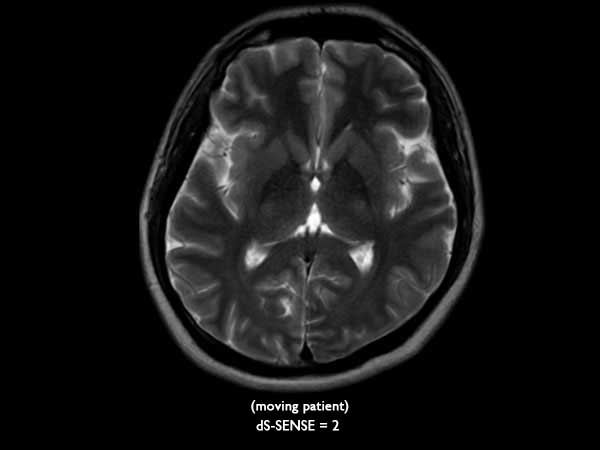

Axial T2w TSE

Axial T2w MultiVane XD